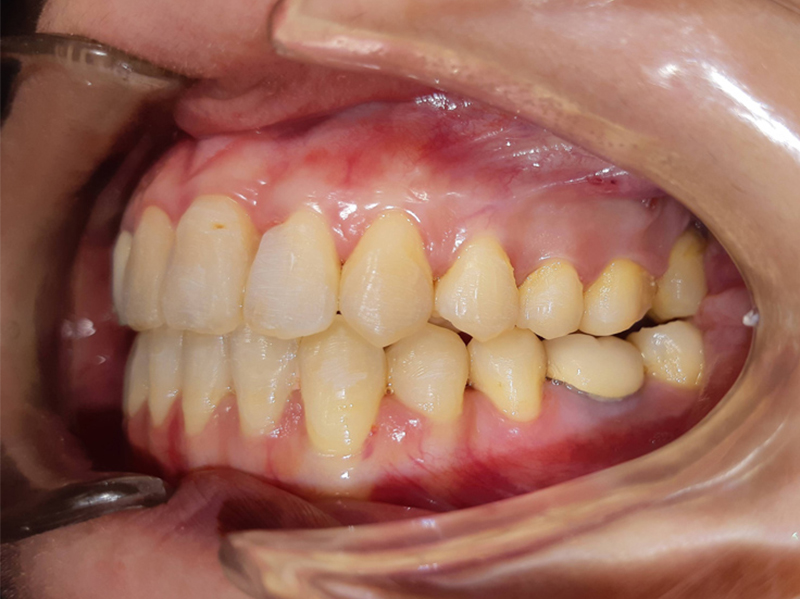

案例:不開刀齒性戽斗前後比較